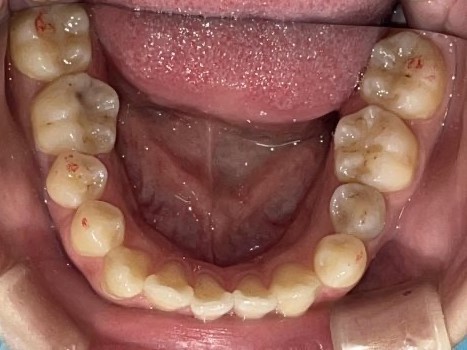

Before

After

矯正の種類 / invisalign GO

年齢・性別 / 30代男性

主訴  /  下の歯の叢生、オーバージェット、交叉咬合

治療期間 / 12ヶ月

費用 / 簡易検査 5,000円(税別) 精密検査 30,000円(税別)

両額マウスピース 450,000円(税別) 両額リテイナー料 40,000円(税別)

※マウスピース交換時別途調節料5,000円(税別)

副作用 / 口内炎・歯の移動に伴う痛み・知覚過敏 ※数日で収まる場合が多いです

リスク / 後戻り防止の為、夜のみマウスピースで保定を指示